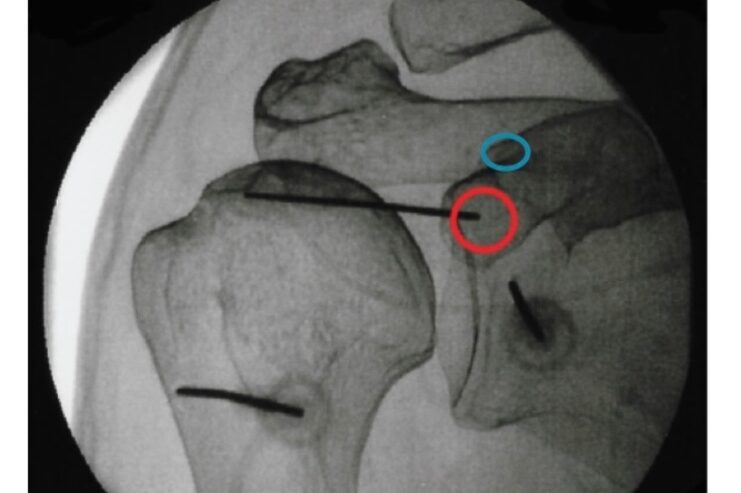

Imaging guided procedures

- Suprascapular nerve block

- SA-SD bursa inj.

- Bicipital inj.

- GH joint inj.

- Acromioclavicular joint inj.

- Aspiration of joint/ cyst/ calcium deposit